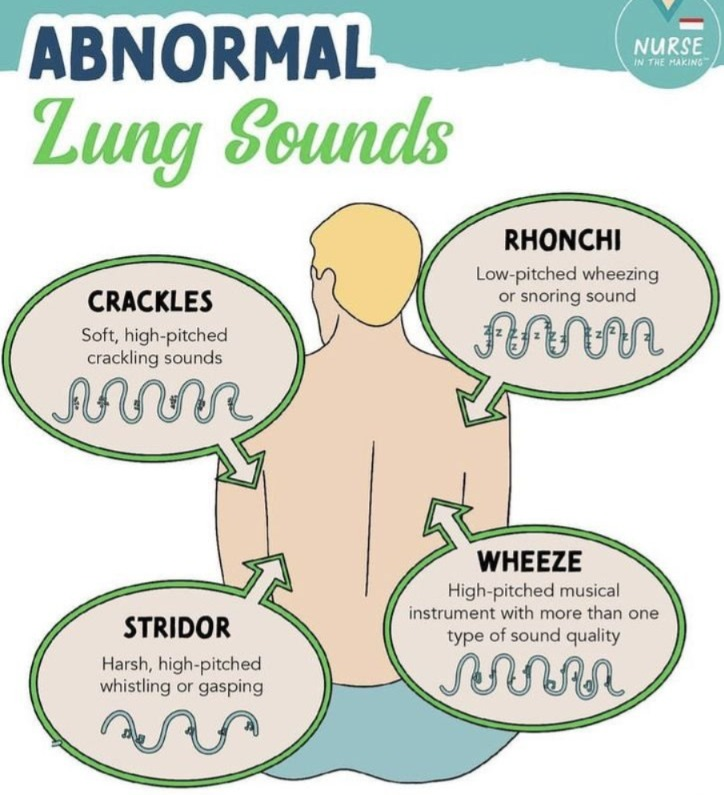

Abnormal lung sound (એબનોર્મલ લંગ સાઉન્ડ):

Wheezing sound (વ્હીઝીંગ સાઉન્ડ):

- વ્હીઝ એ હાઇ પીચ (High-Pitch) મ્યુઝિકલ સાઉન્ડ છે.Wheezing sound ત્યારે થાય છે જ્યારે એરવે (Airway) – એટલે કે breathing passage – Narrowed અથવા Partially Obstructed થઈ જાય છે. વ્હીઝ સાઉન્ડ એ એક્સપીરેશન (શ્વાસ છોડતી વખતે) દરમિયાન જ સંભળાય છે.

Stridor (સ્ટાઇડર):

- સ્ટ્રાઇડર (Stridor) એ એક અબનોર્મલ હાઈ-પિચ્ડ (High-pitched) બ્રીધીન્ગ સાઉન્ડ છે, જે સામાન્ય રીતે ઇન્સ્પિરેશન (Inspiration) દરમિયાન સાંભળાય છે.

આ અવાજ એ સમયે બને છે જ્યારે અપર એરવે (Upper Airway) – ખાસ કરીને લેરિંક્સ (Larynx) અથવા ટ્રેકિયા (Trachea) – નેરો (Narrowed)થઈ જાય છે અથવા ઓબ્સ્ટ્રક્ટેડ (Obstructed) થાય છે. - એટલે કે, Stridor = Inspiratory high-pitched harsh sound due to upper airway obstruction.

Pleural friction rub (પ્લુરલ ફ્રિકશન રબ):

- પ્લ્યુરલ ફ્રિક્શન રબ (Pleural Friction Rub) એ એક અબનોર્મલ રેસ્પીરેટ્રી સાઉન્ડ (Abnormal Respiratory Sound) છે, જે ત્યારે થાય છે જ્યારે પ્લ્યુરલ મેમ્બ્રેન (Pleural Membranes) – એટલે કે Lungsની બહારના Layer પરાઇટલ અને વિસેરલ પ્લુરા (Visceral & Parietal Pleura) – એકબીજા સાથે ઘસાઈ (Rub) જાય છે.

- સામાન્ય રીતે, પ્લ્યુરલ Layer પરાઇટલ અને વિસેરલ પ્લુરા (Visceral & Parietal Pleura) વચ્ચે એક નાની લુબ્રિકેટેડ પ્લુરલ ફ્લુઇડ (Pleural Fluid) હોય છે, જે ફ્રિક્શન અટકાવે છે.

પરંતુ જ્યારે Inflammation થાય છે, ત્યારે આ Layer ખરબચડા (Rough) બની જાય છે અને શ્વાસ લેતી અથવા છોડતી વખતે ઘસારા જેવો અવાજ ઉત્પન્ન કરે છે, અને ગ્રીટિંગ અને ક્રેકિંગ સાઉન્ડ સંભળાય છે. જેને Pleural Friction Rub કહેવામાં આવે છે.

Rhonchi (રહોન્કાય) :

- રહોન્કાય (Rhonchi) એ એક અબનોર્મલ કન્ટિન્યુઅસ બ્રેથ સાઉન્ડ (Abnormal Continuous Breath Sound) છે, જે સામાન્ય રીતે લો-પિચ્ડ (Low-pitched) અને સ્નોરીન્ગ/ ગર્ગલીન્ગ (Snoring / Gurgling) જેવા અવાજ તરીકે સંભળાય છે.

- આ અવાજ મોટાભાગે એરવે (Airway) માં મ્યુકસ (Mucus) અથવા અન્ય સિક્રેશન (Secretions) ભરાય જવાથી બને છે, ખાસ કરીને મોટા બ્રોન્કી (Large Bronchi) માં. જે સામાન્ય રીતે Expiration (શ્વાસ છોડતી વખતે) સંભળાય છે, ક્યારેક Inspiration દરમ્યાન પણ.

Fine crackles (ફાઇન ક્રેકલ્સ):

- ફાઇન ક્રેકલ્સ (Fine Crackles) એ એક પ્રકારનો અબનોર્મલ ડિસ્કન્ટિન્યુઅસ (Discontinuous) બ્રેથ સાઉન્ડ છે, જે Short, Soft, High-pitched Popping or Crackling જેવા અવાજ રૂપે સાંભળાય છે.

- આ અવાજ સામાન્ય રીતે Inspiration (શ્વાસ લેતી વખતે) દરમ્યાન સાંભળાય છે, ખાસ કરીને Lungsના બેઝ (Bases) પર.

તે દર્શાવે છે કે lungsના નાના એરવે અથવા એલ્વિઓલાઈ (Alveoli) માં પ્રવાહી (Fluid) અથવા કોલેપ્સ થયેલા એર સ્પેસ (Collapsed Air Spaces) ખુલતાં હોય છે.

Coarse crackles (કોર્સે ક્રેકલ્સ):

- કોર્સ ક્રેકલ્સ (Coarse Crackles) એ એક પ્રકારના અબનોર્મલ બ્રેથ સાઉન્ડ્સ (Abnormal Breath Sounds) છે, જે Long, Loud અને Low-pitched “બબલિંગ / ગર્ગલિંગ અવાજ (Bubbling or Gurgling Sound)” જેવા લાગે છે.

- આ અવાજ સામાન્ય રીતે Inspiration અને Expiration બંને દરમ્યાન સાંભળાય છે અને Lungsના મોટા એરવે (Larger Airways) માં મ્યુકસ (Mucus) અથવા ફ્લુઇડ (Fluid) Accumulation થવાથી ઉત્પન્ન થાય છે.